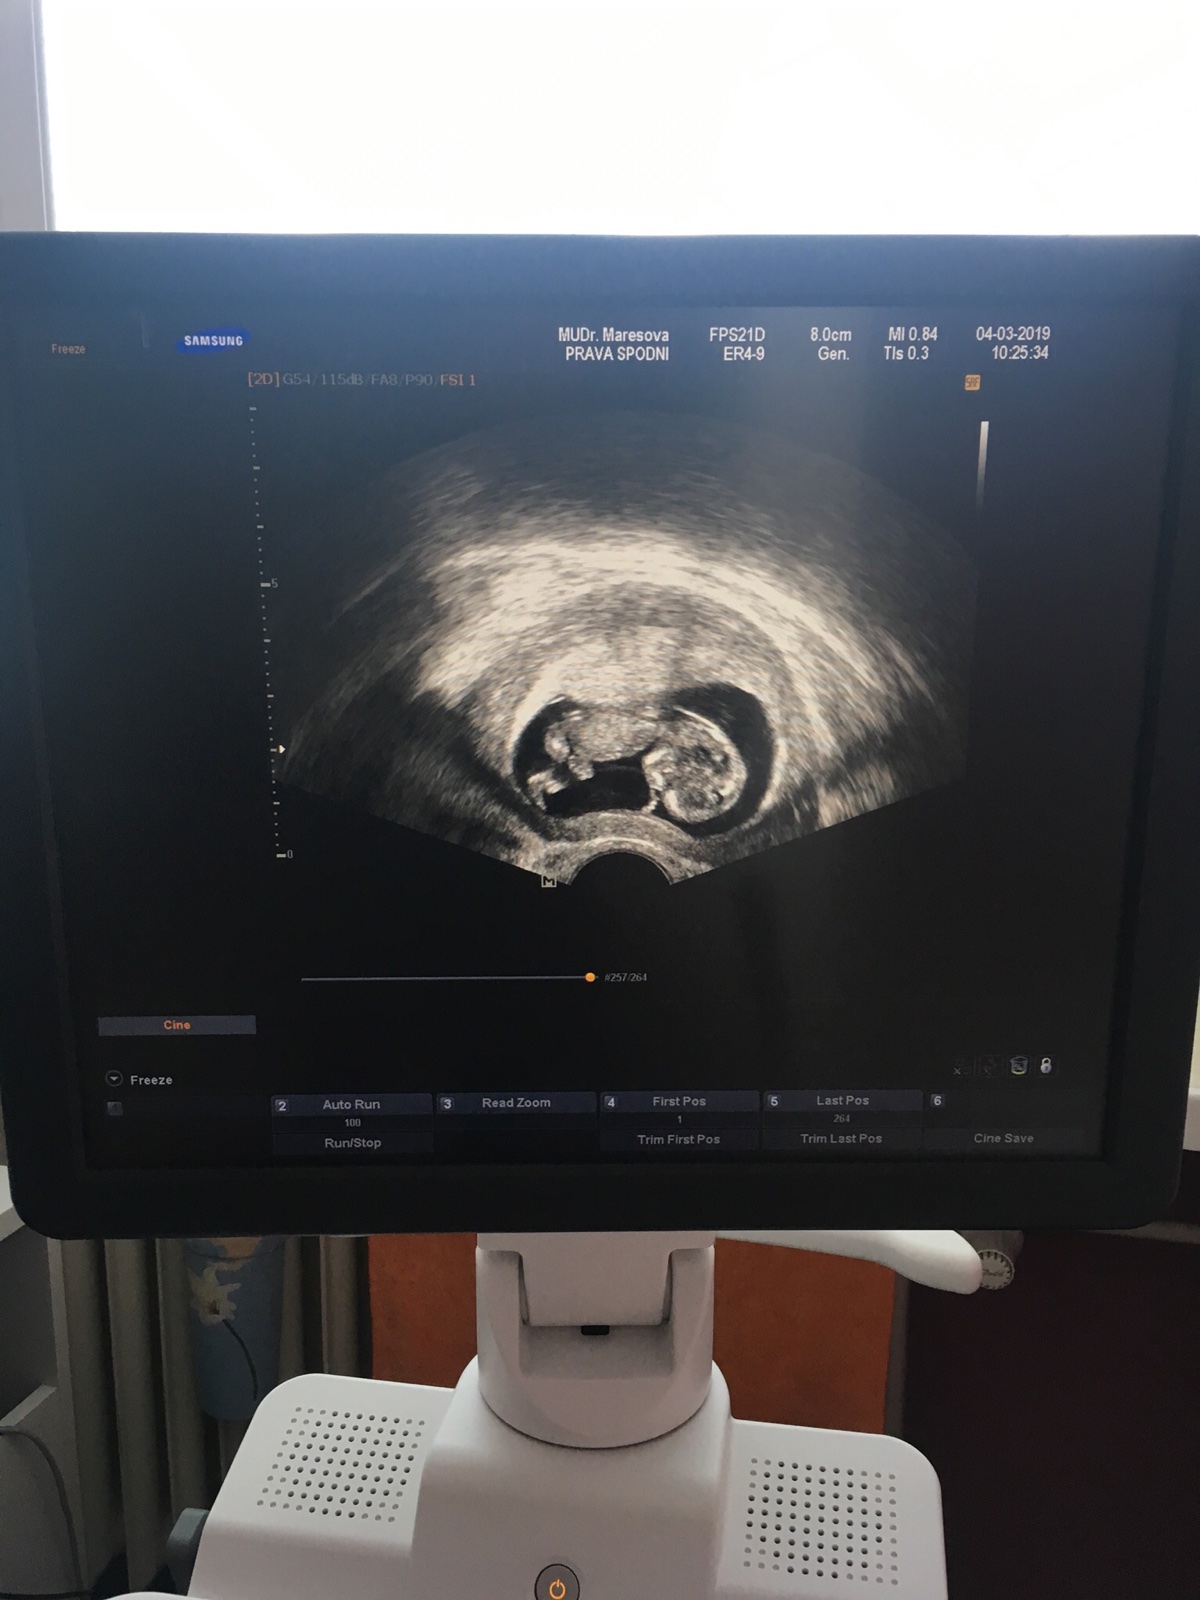

V sobotu ráno jsem ani neměla náladu vstát a fungovat, oba jsme nemohli spát. Ve mě se to přes noc srovnalo a začala jsem předchozího dne hořce litovat. Rozhodla jsem se, že si přes den sedneme a budu chtít slyšet názor přítele. Příteli se to asi rozleželo v hlavě, bylo na něm vidět, že to dítě chce. Je z děckého domova o to více mě to mrzelo, chtěl rodinu, kterou nikdy neměl a já mu tu možnost chtěla vzít, protože jsem prostě byla srab. Zazněly argumenty, že mě je 25 jemu skoro 27 a máme na to už věk navíc jsme tu dobu byly spolu už 7 let. Vnitřně jsem si dítě chtěla nechat, ale z venčí jsem proste propadala panice, neměli jsme ani našetřeno. Já jsem si stále připadala jako dítě. Bylo mi hrozně líto přítele měl stejné právo rozhodnout jak to bude dál a já ho postavila před hotovou věc. Jeho poslední věta byla, že je to moje tělo a mám se rozhodnout sama jak to bude dál, ale mám si i uvědomit, že se to potom taky nemusí podařit. Neuměla jsem si představit, ze mi táhne na 30 a mám nervy v kýblu, protože nemůžu otěhotnět. Po probrečeném víkendu jsem nakonec uznala, že si prcka necháme. V tu chvíli se ve mě něco zlomilo, byla to taková úleva a neskutečný nával radosti, která se stupňovala každým ultrazvukem. 🙂